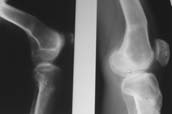

Пациент В. 53 лет, травма в феврале 2009. ДЗ. Открытый оскольчатый перелом нижней трети голени. При боли поступлении выполено ПХО, аппарат Илизарова. В последующем проводили ВХО, резекция костных отломков, укорочение 6 см, рана зажила. Была выполнена остеотомия большеберцовой кости в проксимальном отделе, резекция. Производилось тракция. На последних рентгенограммах выявлено, что одновременно с "выращиванием" регенерата произошло низведение надколенника на длину выращенного регенерата. Клинически: активное разгибание сохранено, объем движений в колене 180-110 градусов. Черными стрелками обозначен верхний край надколенника с одной и с другой стороны. Красная стрелка обозначает пальпируемую связку надколенника. Причина - остеотомия выше места прикрепления связки надколенника. Вопрос: была ли у кого подобная ситуация? Что делать? При первом обдумывании приходит решение: отсечение места прикрепления связки надколенника с костным блоком, перемещение на "правильное" место, укорочение сухожилия четырехглавой мышцы.